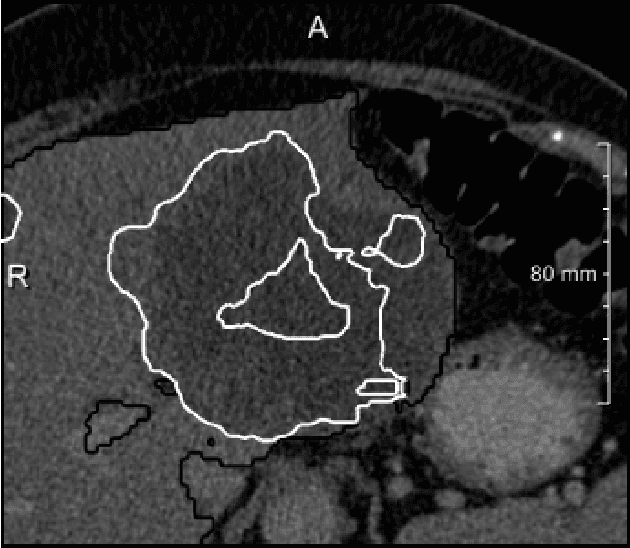

Abstract:In this work, we report the set-up and results of the Liver Tumor Segmentation Benchmark (LITS) organized in conjunction with the IEEE International Symposium on Biomedical Imaging (ISBI) 2016 and International Conference On Medical Image Computing Computer Assisted Intervention (MICCAI) 2017. Twenty four valid state-of-the-art liver and liver tumor segmentation algorithms were applied to a set of 131 computed tomography (CT) volumes with different types of tumor contrast levels (hyper-/hypo-intense), abnormalities in tissues (metastasectomie) size and varying amount of lesions. The submitted algorithms have been tested on 70 undisclosed volumes. The dataset is created in collaboration with seven hospitals and research institutions and manually reviewed by independent three radiologists. We found that not a single algorithm performed best for liver and tumors. The best liver segmentation algorithm achieved a Dice score of 0.96(MICCAI) whereas for tumor segmentation the best algorithm evaluated at 0.67(ISBI) and 0.70(MICCAI). The LITS image data and manual annotations continue to be publicly available through an online evaluation system as an ongoing benchmarking resource.

Abstract:We present a fully automatic method employing convolutional neural networks based on the 2D U-net architecture and random forest classifier to solve the automatic liver lesion segmentation problem of the ISBI 2017 Liver Tumor Segmentation Challenge (LiTS). In order to constrain the ROI in which the tumors could be located, a liver segmentation is performed first. For the organ segmentation, an ensemble of convolutional networks is trained to segment a liver using a set of 179 liver CT datasets from liver surgery planning. Inside of the liver ROI a neural network, trained using 127 challenge training datasets, identifies tumor candidates, which are subsequently filtered with a random forest classifier yielding the final tumor segmentation. The evaluation on the 70 challenge test cases resulted in a mean Dice coefficient of 0.65, ranking our method in the second place.